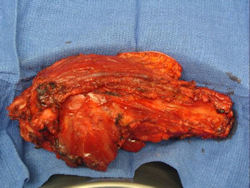

Gross Pathology: Conventional Osteosarcoma

These are examples of the gross pathology specimens of resected conventional osteosarcoma, consisting of both bony and soft tissue areas. X-rays of the specimens are included.

- Osteosarcomas are composed of ossified or non-ossified tissue

- Ossified tissue is yellow-white and hard

- Less ossified tissue is soft and less yellow

- Non-ossified tissue is tan and fleshy

- Most (95%) of conventional osteosarcomas penetrate the cortex and form a large extraosseous soft tissue mass

- The lesion permeates the marrow spaces

- Osteosarcomas usually infiltrate the marrow several centimeters away from the main tumor mass

- Osteosarcomas may also have cartilaginous components that appear as translucent lobules, and/or fibrous components that are tan, soft to firm rubbery areas

- Osteoblastic areas are usually white to yellow, firm, hard and gritty

- The consistency of the tumor depends on the amount of osteoid deposition, cartilaginous and fibrous areas

- Foci of hemorrhage and necrosis are common